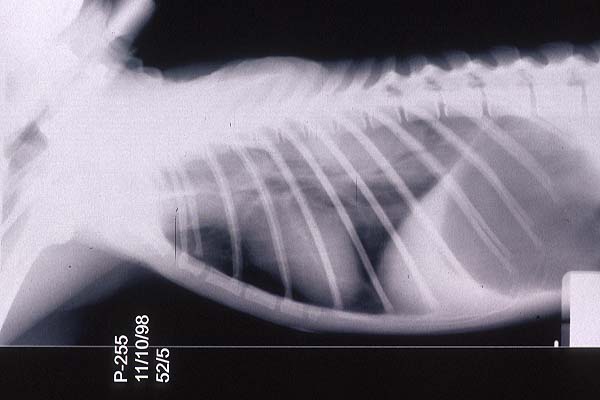

- Case 23-3. The A/P thoracic radiograph shows marked

right sided deviation of the cardiac silouette. The lateral thoracic

radiograph shows diffuse fluid density in dorsal lung fields.

- Thoracic radiographs demonstrated an increased pulmonary

interstitial pattern with air bronchograms bilaterally. The cardiac

silhouette was shifted to the right. Abdominal radiographs demonstrated